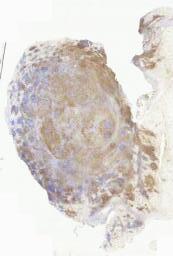

免疫组化: CK(pan)(+),EMA(灶+),S-100(+),P63(个别+),CK7(-),GFAP(-),SOX-10(-),CD34(血管+),CD117(-),Desmin(-),SMA(-),p53(+,野生型),p16(-),SATB2(-),Calponin(-),CDK-4(-),MDM2(-),INI-1(未缺失),Ki-67(约5%)。